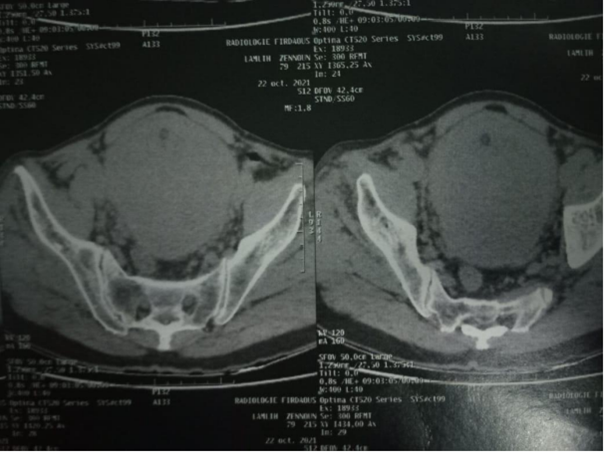

obstructive urinary symptoms, but had no hematuria or urinary incontinence. During physical evaluations, a firm  prostate with an unidentified border was detected through digital rectal examination due to its sizable volume. All laboratory tests came back normal except for total prostate-specific antigen, which registered at 10.9 ng/mL. Additionally, transrectal ultrasound measured the volume of the patient's prostate to be 250 mL. During the ultrasonography examination, a large prostatic mass was identified by the radiologist. This mass had caused displacement of the bladder towards its right side. Additionally, confirmation from the CT-scan revealed that indeed it was originating from prostate tissue (Figures 1 and 2).

Figure 1 and 2 Computed tomography scan showing the huge prostate filling the bladder.